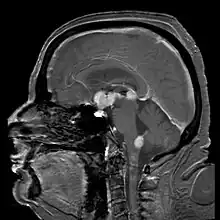

| Brain magnetic resonance imaging showing primary central nervous system B-cell non-Hodgkin lymphoma of the sella turcica and hypothalamus, continuing to the tectum (intensely white areas in the middle). | |